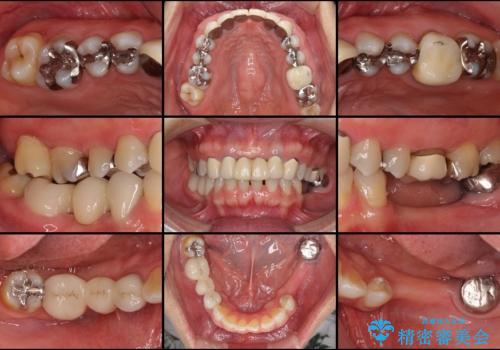

- 口の中に気になるところが沢山あるものの、地元ではなかなか治療を行ってくれるところがないとのことで、沖縄県の離島より来院された患者様です。

金属を使用した前歯のブリッジや奥歯の銀歯は全てオールセラミッククラウンまたはセラミックインレーとし、左下の奥歯はインプラントにより治療を行うこととしました。

外科処置を行うため、治癒を待つ期間が数ヶ月あるため、その期間を利用して下顎前歯のスペースを矯正治療で閉じることとしました。